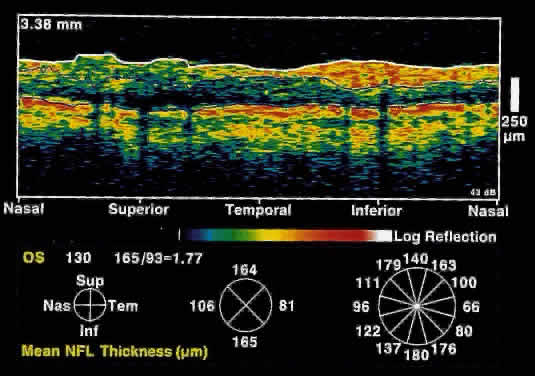

only after up to 50% of retinal nerve fibers have been lost. OCT, because of its high resolution, is able to detect nerve fiber layer

thinning before the onset of visual changes.21 Nerve fiber layer thickness, as measured by OCT, has been shown to correspond

to visual function. As expected from the histology of the peripapillary

retina, the nerve fiber layer is thickest in the inferior and

superior quadrants. The nerve fiber layer has been demonstrated to be

significantly thinned in areas corresponding to visual field loss. Typically, the scans are performed radially around the optic nerve for 360° using

two radii of curvature (2.25 and 3.37 mm), and the nerve

fiber layer thickness is plotted schematically (Fig. 16). Normal nerve fiber layer thickness is a mean of 148.6 microns for superior

nerve fibers, 143.5 microns for inferior nerve fibers, 66.9 microns

for temporal nerve fibers, and 117.2 for nasal nerve fibers. The

direct measurement of the nerve fiber layer thickness by OCT is an objective

assessment of glaucomatous progression. OCT shows promise in the

early diagnosis of glaucoma before visual field defects, optic nerve

head changes, and ophthalmoscopically visible nerve fiber layer loss

are evident.  Fig. 16. Circular OCT image of a normal eye taken in cylindrical section around

the optic nerve head. Note the thicker nerve fiber layer superiorly and

inferiorly. Fig. 16. Circular OCT image of a normal eye taken in cylindrical section around

the optic nerve head. Note the thicker nerve fiber layer superiorly and

inferiorly.